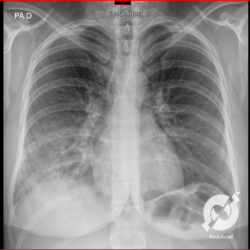

E o nome dado a esta alteração radiográfica que corresponde à substituição do ar alveolar por líquido é a consolidação alveolar.

Uma consolidação alveolar é, por definição, uma opacidade (imagem densa, branquinha) homogênea ou às vezes heterogênea (pela presença de calcificações ou cavidades), de limites mal definidos, exceto quando toca a pleura da parede ou das cissuras pulmonares. É um termo usado tanto em radiografia, como em tomografia computadorizada. Na tomografia, um outro termo é usado: vidro fosco, que é uma opacidade (branquinha mas não tanto como a consolidação), que borra o pulmão mas deixa ver os vasos de permeio (igual bigode de adolescente: dá pra ver todo o fundo).

Nós vamos mostrar aqui um pequeno apanhado de pneumonias de variados agentes, em diversos segmentos e lobos pulmonares, com extensões variadas. O objetivo é identificar o padrão radiológico de consolidação alveolar e não determinar o agente infeccioso, isso vai ser assunto para mais adiante. Aliás já antecipo que é fundamental saber localizar a lesão, porque alguns destes bichos gostam de determinados segmentos, alguns tumores também têm as suas preferências, então localização é fundamental. Se localização não fosse importante, um apartamento na beira do mar sairia o mesmo preço de um apartamento de frente pra BR-101, concordam?

Seguem alguns dos nossos casos de pneumonia para vocês treinarem os olhos e não se apavorarem nos plantões.